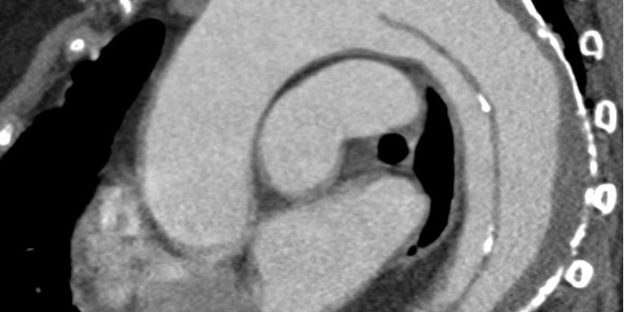

Diagnoseverfahren

Die Diagnostik einer Aortendissektion erfordert eine schnelle und präzise Bildgebung. Das wichtigste Verfahren, das eine gesicherte Diagnose liefert, ist die Computertomographie bzw. die CT-Angiografie. Sie liefert detaillierte Schnittbilder und zeigt die Ausbreitung der Dissektion.